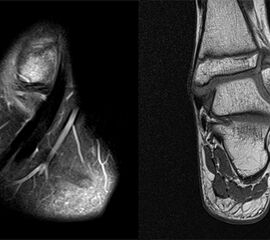

MRT

Die Kernspintomographie hat ihre Stärke in der Darstellung von Weichteilverletzungen. Insbesondere Verletzungen der Wachstumsfuge, des Periosts und der Bänder lassen sich gut visualisieren. Nachteilig ist die Untersuchungsdauer von 20-30 Minuten. Bleibt das Kind während dieser Zeit nicht ruhig liegen, kommt es zu Bewegungsartefakten, welche die Beurteilbarkeit der Bilder beeinträchtigen.

• Einblutung und Ödemzone im MRT

Fugengelenkfrakturen treten typischerweise vor dem 10. Lebensjahr auf, in einer Phase, in welcher die Wachstumsfugen noch weit offen sind. Dieser Frakturtyp betrifft fast ausschließlich den medialen Malleolus. Laterale Frakturen sind extrem selten, teilweise kommt es zu lateralen Bandverletzungen oder Fugenschaftfrakturen der distalen Fibula. Die Frakturlinie verläuft in einer Verlängerungslinie von der medialen Taluskante nach proximal. Häufig stellen sich Verletzungen des Innenknöchels im Röntgenbild schlechter dar, insbesondere wenn die Aufnahmen verdreht sind oder die Ebene der Fraktur bei geringer Dislokation verkippt zur Röntgenebene liegt. Besteht klinisch der geringste Hinweis auf eine Verletzung des Innenknöchels, muss aufgrund der Tragweite der Verletzung durch entsprechende Aufnahmen gegebenenfalls auch Schnittbildverfahren die Verletzung sicher diagnostiziert oder ausgeschlossen werden (Abb. 15).